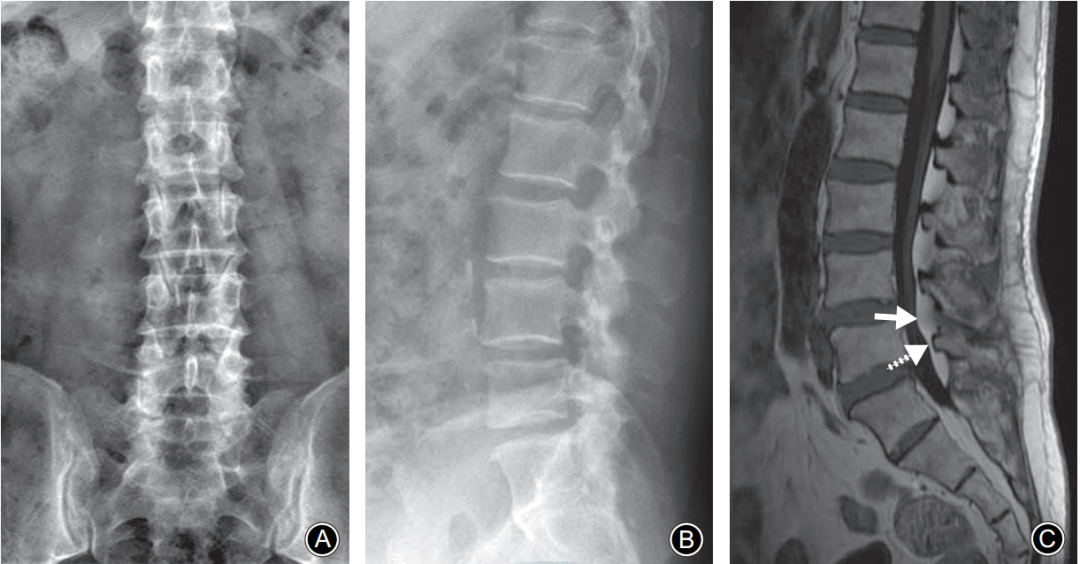

腰椎MRI正中矢状面 T1WI。A:棘突基底部和硬膜之间未见脂肪沉积;B:L5棘突基底部与硬膜之间可见线状脂肪高信号带(箭头示)

L5椎弓峡部裂典型病例一:男,32岁。A,B: 腰椎正位侧位X线片示无明显椎弓峡部裂征象; C: 腰椎 MRI正中矢状面T1WI示L5棘突基底部与硬膜之间出现脂肪高信号带(箭头示); D: 腰椎CT矢状面重建示L5椎弓峡部骨质不连(箭头示)。

L5椎弓峡部裂典型病例二:男,35岁。A,B: 腰椎正位侧位X线片均无明显椎弓峡部裂征象; C: 腰椎MRI正中矢状面T1WI示L5棘突基底部与硬膜之间出现脂肪高信号带(箭头示); D: 腰椎CT矢状面重建示L5椎弓峡部骨质不连,裂隙较细(箭头示)。

峡部裂引起的硬膜外脂肪增多应与单纯椎管内脂肪增多相鉴别。

• 与峡部裂仅局限于棘突基底部不同,单纯硬膜外脂肪增多除了位于棘突基底部外,更常见的部位为椎板与硬膜之间。

• 硬膜外脂肪沉积的形态表现各异。峡部裂患者常表现为线状,而脂肪增多患者在椎板下方表现为半弧形,且部分单纯脂肪增多患者因脂肪占位而导致椎管狭窄,出现相应的间歇性跛行症状。

• 两者受累的节段也存在差异。峡部裂多发生于L5节段,而单纯硬膜外脂肪增多更多位于L3和L4峡部。